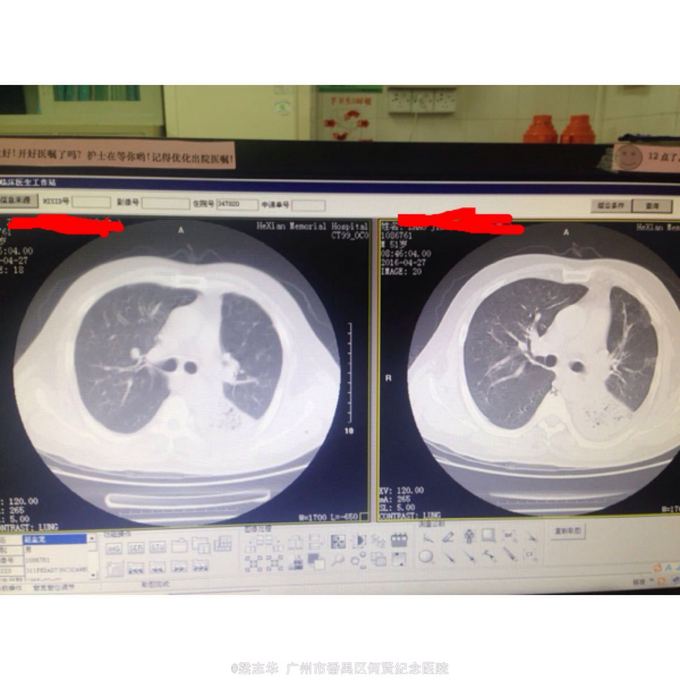

体查:T:36.8℃ R: 20次/分 P:110次/分 BP:130/76mmHg,全身浅表淋巴结未扪及肿大,胸廓对称无畸形、无局部膨隆或凹陷。呼吸平稳,节律规则。双侧呼吸动度对称。双肺部叩诊清音。左下肺呼吸音低,左下肺可闻及较多痰鸣音。心界不大,心率110次/分,律齐,各瓣膜区未闻及病理性杂音。 辅助检查:2016-04-23 血常规:WBC-LE 17.7 10^9/L ↑ NEUT#-LE 14.75 10^9/L ↑ NEUT%-LE 83.2 % ↑ KS-CRP >200 mg/L ↑ 。2016-04-24 ESR 98.0 mm/h ↑ 。2016-04-27 HBA1C 6.1 % ↑ 。双肺CT:1、右肺中叶及左肺上叶舌段、下叶支气管扩张并感染;左肺下叶多发空洞,考虑肺脓肿;右肺中叶肺不张、左肺下叶膨胀不全。2、左侧少量胸腔积液。3、双侧胸膜增厚、粘连。4、轻度脂肪肝。入院后血糖在5.6~9.3mmol/h。

诊断: 1.肺炎伴肺脓肿. 治疗:入院后予吸氧抗炎(莫西沙星)化痰等治疗,并行左侧胸腔穿刺术,但术中未能抽出脓液,经上述治疗,患者症状好转,体温逐渐下降。